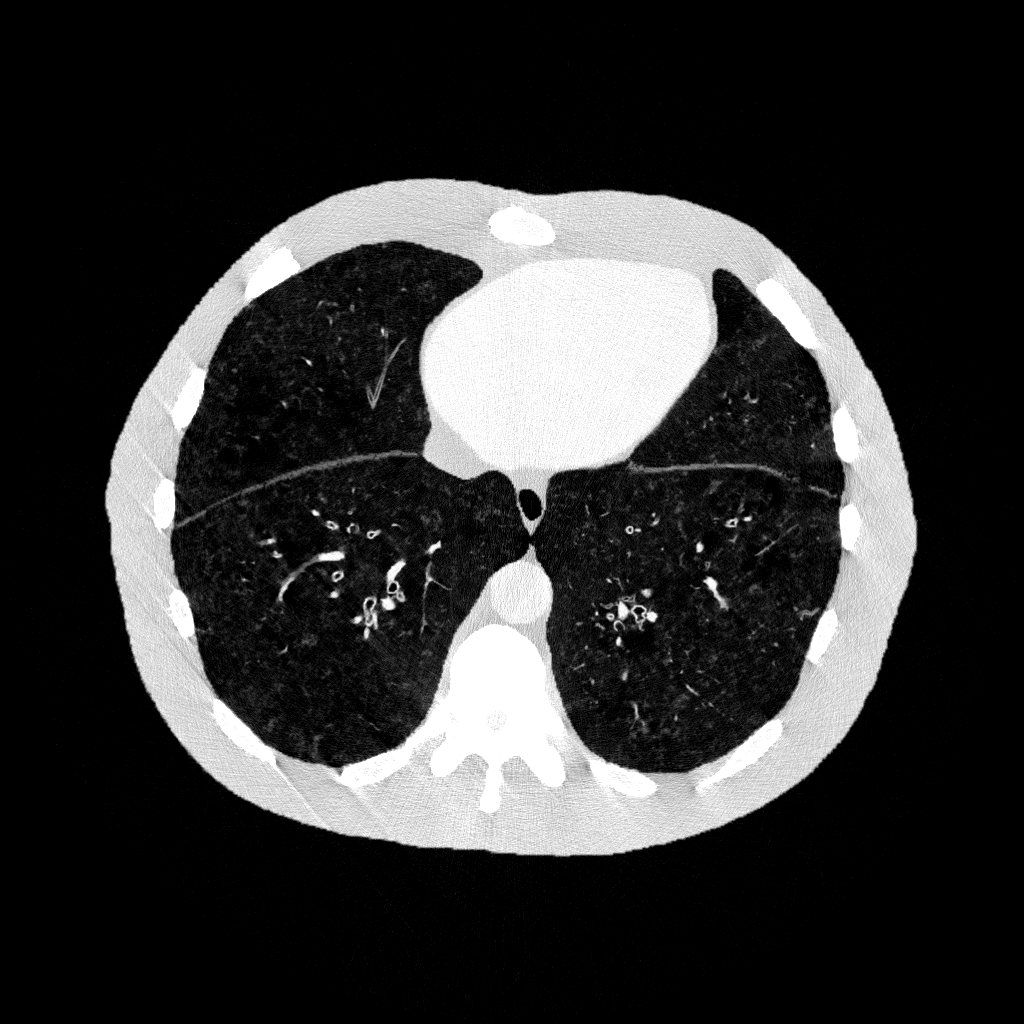

Example datasets: axial cross-sectional 3D CT images of a digital human phantom with COPD, generated using DukeCounter photon-counting CT scanners

Images from CZT-based DukeCounter Scanner